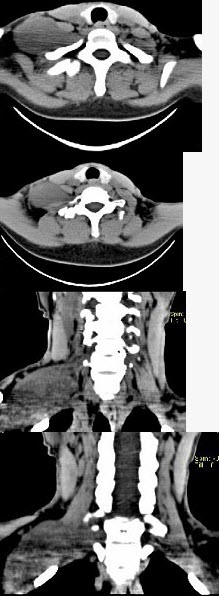

女,47岁,下颈部触及一包块约五年余,CT如图所示,最可能诊断为()。

A、滑膜肉瘤

B、血管瘤

C、神经鞘瘤

D、副神经节瘤

E、巨淋巴结增生症

C